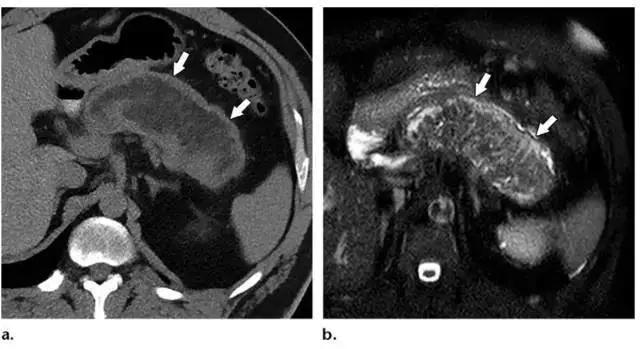

4 周以后,ANC 逐渐形成成熟的壁,进展为 WON。同假性囊肿相似,WON 包括液性物质和可明显强化的厚壁。但与假性囊肿不同的是,WON 含有坏死脂肪或胰腺组织,在增强 CT 和 MR 图像中表现为液体内含有非液性成分(图 3c,10)。

WON 可存在于胰腺实质,但更常见于胰周,也可同时累及胰腺和胰周(图 10)。有研究表明,对于病程超过 4 周胰腺炎,MR 的评估能力高于 CT。

MR 成像可以显示坏死物的数量,因此在制作手术计划时,MR 成像可作为增强 CT 的替代方法(图 11)。

图 10 48 岁坏死性胰腺炎女性患者 2 个月内的演变过程。a 1 周:轴位增强 CT 示胰颈坏死(*)。b 2 周:轴位增强 CT 示新发胰颈(*)坏死相连的胰周(箭头)坏死,征象符合 ANC。c 3 周:周围 T2WI MR 图像更清晰的显示了 ANC(*)的内容物,包括液性高信号和非液性坏死物,后者又包括胰颈和胰体的坏死(箭头)。注意局部壁形成。d 5 周:轴位增强 CT 示成熟壁形成,符合 WON(*)的诊断。e 囊肿胃引流术和清创术中内镜可见 WON 排出的坏死物(箭头)。f 7 周:术后增强轴位 CT 图像可见 WON 已成功清除,可见双尾支架影

图 11 发病 16 周的 47 岁男性坏死性胰腺炎患者。a 轴位平扫 CT 图像示几乎累及整个胰腺的 WON(箭头),约有一半为液性密度。b 随后轴位脂肪抑制 T2WI MR 图像示 WON(箭头)大部分为非液性坏死物和胰腺坏死,仅有少量液体信号。这样的病灶经皮或内镜引流效果差,需要创伤性更大的治疗方法